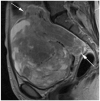

Results: Four qualitative MR features most strongly associated with LMS were nodular borders, haemorrhage, "T2 dark" area(s), and central unenhanced area(s) (p ≤ 0.0001 each feature/reader). The highest sensitivity [1.00 (95%CI:0.82-1.00)/0.95 (95%CI: 0.74-1.00)] and specificity [0.95 (95%CI:0.77-1.00)/1.00 (95%CI:0.85-1.00)] were achieved for R1/R2, respectively, when a lesion had ≥3 of these four features. Sixteen texture features differed significantly between LMS and ALM (p-values: <0.001-0.036). Unsupervised clustering achieved accuracy of 0.75 (sensitivity: 0.70; specificity: 0.79).

Key points: • Four qualitative MR features demonstrated the strongest statistical association with LMS. • Combination of ≥3 these features could accurately differentiate LMS from ALM. • Texture analysis was a feasible semi-automated approach for lesion categorization.